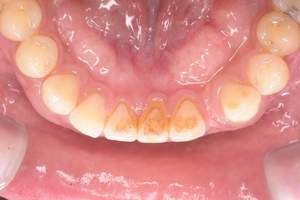

歯石除去

治療前

治療後

| 年齢 | 36歳・男性 |

| 主訴 | 歯石をとりたい |

| 治療内容 | 歯石除去 |

| 治療期間 | 30分 |

| 費用 | 約2,000円 |

| リスク・副作用 | ・歯ぐきの炎症が強いと歯石を取る際に出血することがあります。 ・処置後に歯がしみることがあります。 ・歯と歯の間に隙間ができるので、息が漏れ発音しにくいと感じることがあります。 ・歯ぐきの炎症が軽減すると歯ぐきが引き締まり、歯が長く見えることがあります。 |